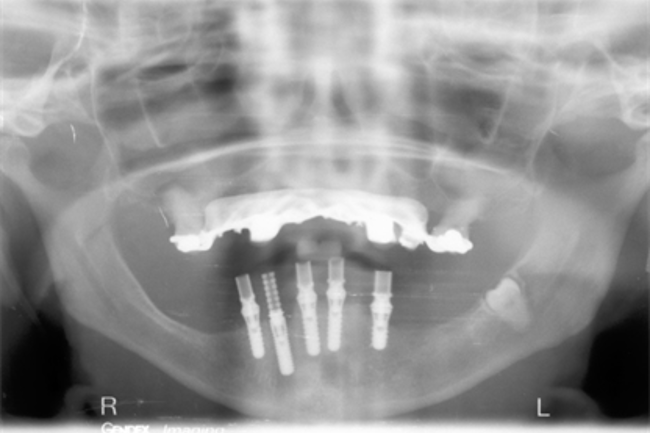

What happens if you have a case like the one below where you have preps and implants?

This is an example of a bigger case – one where we wanted to be able to incorporate the fixture position of the implants into the model.

You can see in the series of images below, courtesy of Ashley Bryne, how we did this.

So now we had the benefits we were seeing with routine work and in our implant cases/combined cases.

Next up – the use of Simplant imaging

What next? We were using Simplant for some of our implant cases,. But we felt we were still missing something.

So, with the help of Barry Chandler, we started to merge the pre-op intra oral scans with the Simplant planning.

It is my understanding that we were the first people to do this in the UK and possibly Europe.

An example of one of the first cases that we did this way is below, including the most recent images of the case.

This illustrates the power of guided surgery and constant improvement.